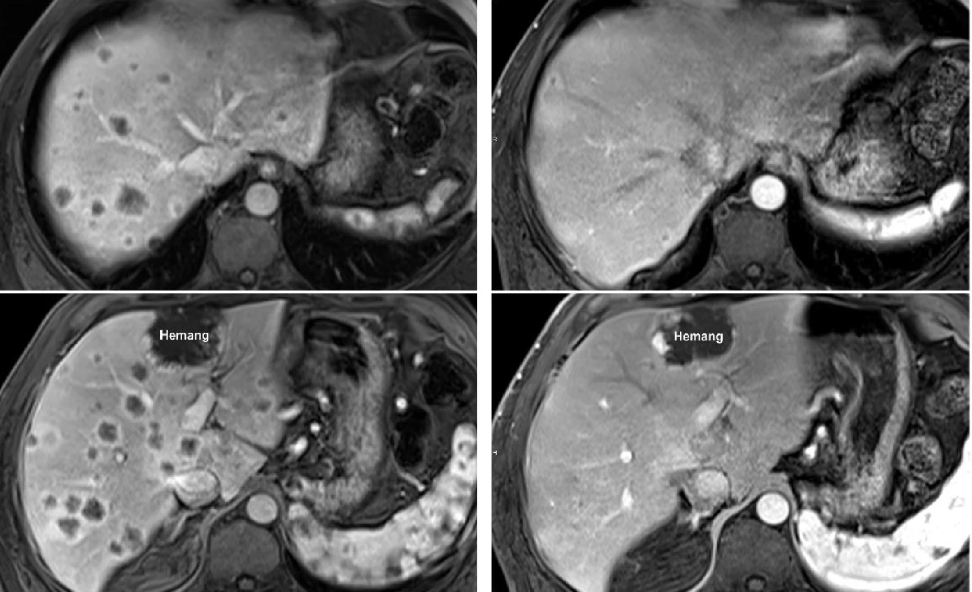

在过去的几年中,细胞免疫疗法为癌症治疗提供了一种新的策略。最近的临床研究表明,肿瘤浸润淋巴细胞(TIL)治疗在晚期实体瘤的治疗中显示出良好的疗效,这为癌症患者带来了新的希望。

近年来,癌症治疗领域迎来了一场革命性的变化。从传统的手术、化疗和放疗到靶向治疗和免疫治疗,科学技术的进步不断重塑着癌症治疗的模式。其中,细胞免疫治疗作为有前途的方向之一,受到越来越多的关注。在各种细胞免疫疗法中,肿瘤浸润淋巴细胞(TIL)疗法近年来尤为突出,甚至在一些晚期癌症患者中取得了惊人的“临床治愈”效果。

在过去的几年时间里,细胞免疫疗法已经逐步成为了癌症治疗的有力策略。其中,肿瘤浸润淋巴细胞(TIL)疗法在实体瘤治疗中的临床应用显示出良好的疗效。